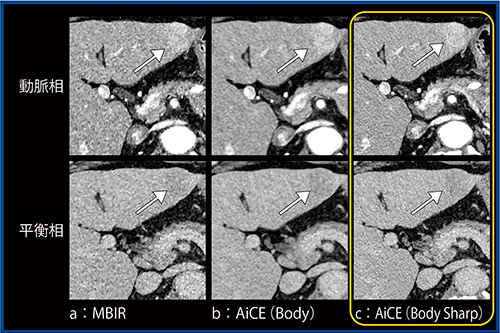

前出の原発性HCC症例(70歳代,男性)について,AiCE(Body Sharp)で再構成した(図2 c)。AiCE(Body)(図2 b)と比べるとノイズは若干増えているものの,腫瘍境界の視認性(→)が改善されている。また,MBIR(図2 a)と比べてAiCE(Body Sharp)では,低周波ノイズは目立たなくなっている。

図2 MBIR,AiCE(Body),AiCE(Body Sharp)の比較

(図1と同一症例)